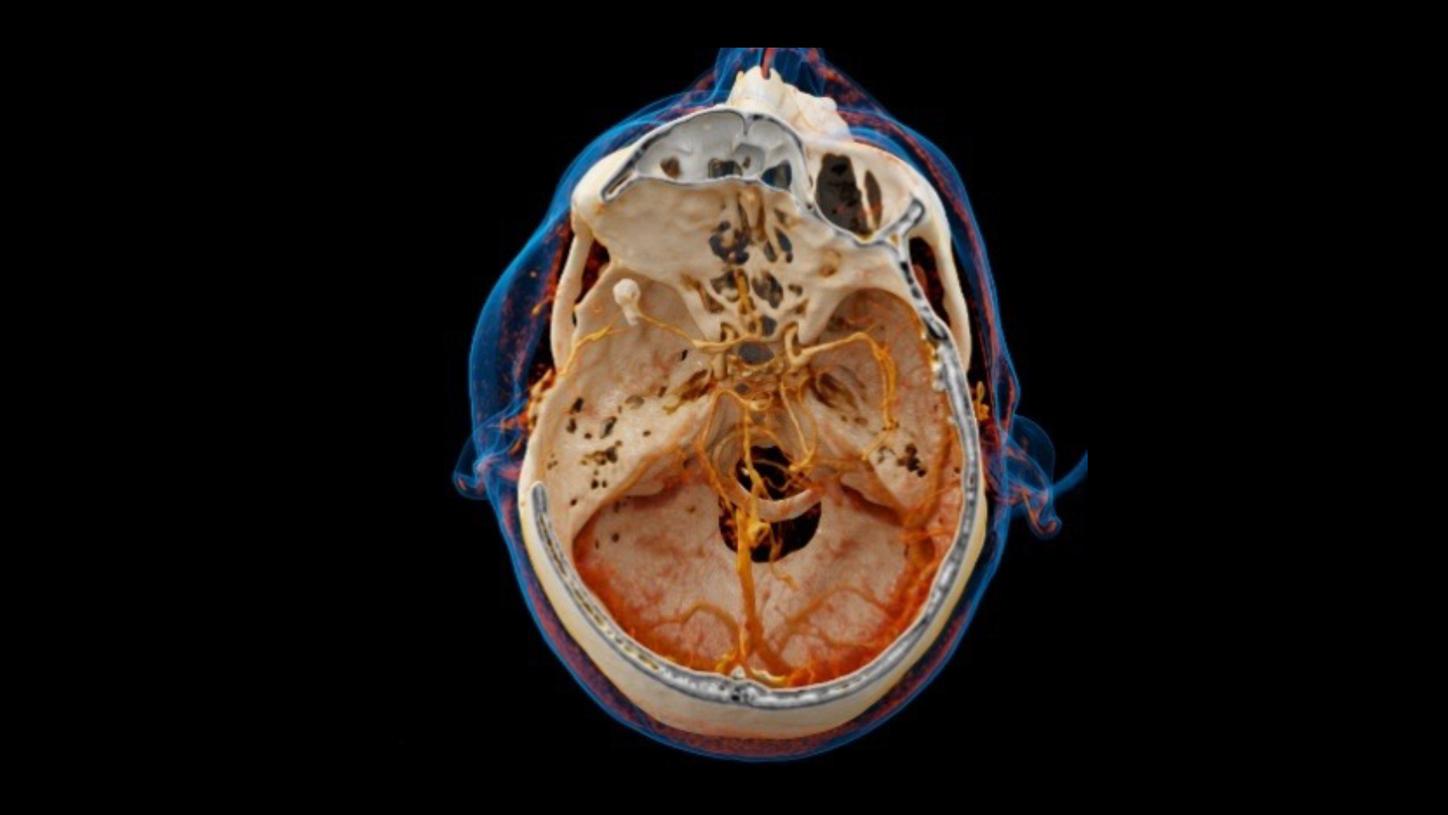

Cinematic VRT

Clearly visualize clots and get photorealistic and easy-to-understand material for education, publication, and communication